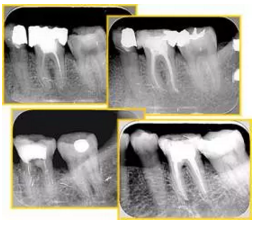

共有 4 張 X 線片,分別是術(shù)前、診斷絲 、主牙膠尖確認(rèn)、術(shù)后。

( 1 )術(shù)前:術(shù)前 X 線片用來了解牙齒的大概情況。術(shù)前預(yù)期為多根牙時 X 線片應(yīng)偏頭拍攝。

( 2 )診斷絲:根據(jù)術(shù)前 X 線片進(jìn)行開髓、根管的初步預(yù)備后,需要插入診斷絲,用來指示工作器械位置。常用 10 號或 15 號擴(kuò)大器作為診斷絲插入牙髓腔。

( 3 )主牙膠尖確認(rèn):通過術(shù)前預(yù)期和診斷絲診斷,明確工作長度、牙根走向,進(jìn)行根管預(yù)備。之后應(yīng)進(jìn)行主牙膠尖(中銼)確認(rèn),已明確根管是否適合充填。

( 4 )術(shù)后:觀察治療效果。

6. 術(shù)后 X 線片

術(shù)后 X 線片用來評定根管充填 長度、致密度(管壁清晰、側(cè)枝)等指標(biāo)。

圖為根管充填術(shù)后 X 線片。圖中可見,根管充填較好。右下圖有白色小點(diǎn),為側(cè)方加壓導(dǎo)致糊劑擠出所致,表明根管充填比較致密。

多根牙時候需進(jìn)行偏移投照,正位投照無法說明具體哪根牙根管充填效果。